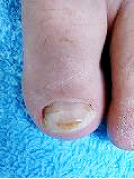

長期のハイヒール靴使用による巻き爪

矯正前